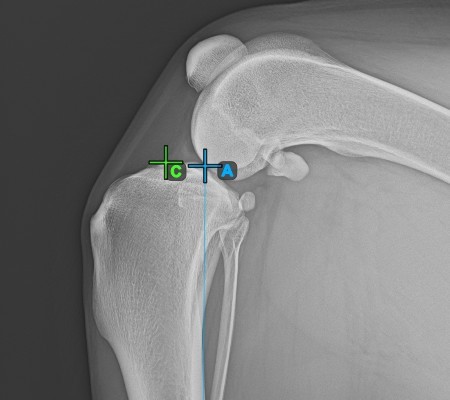

Once the long axis of the tibia has been identified, mark the most cranial point of the tibial head (tibial plateau).

The image below depicts the usual placement of the most cranial point on the tibial plateau.